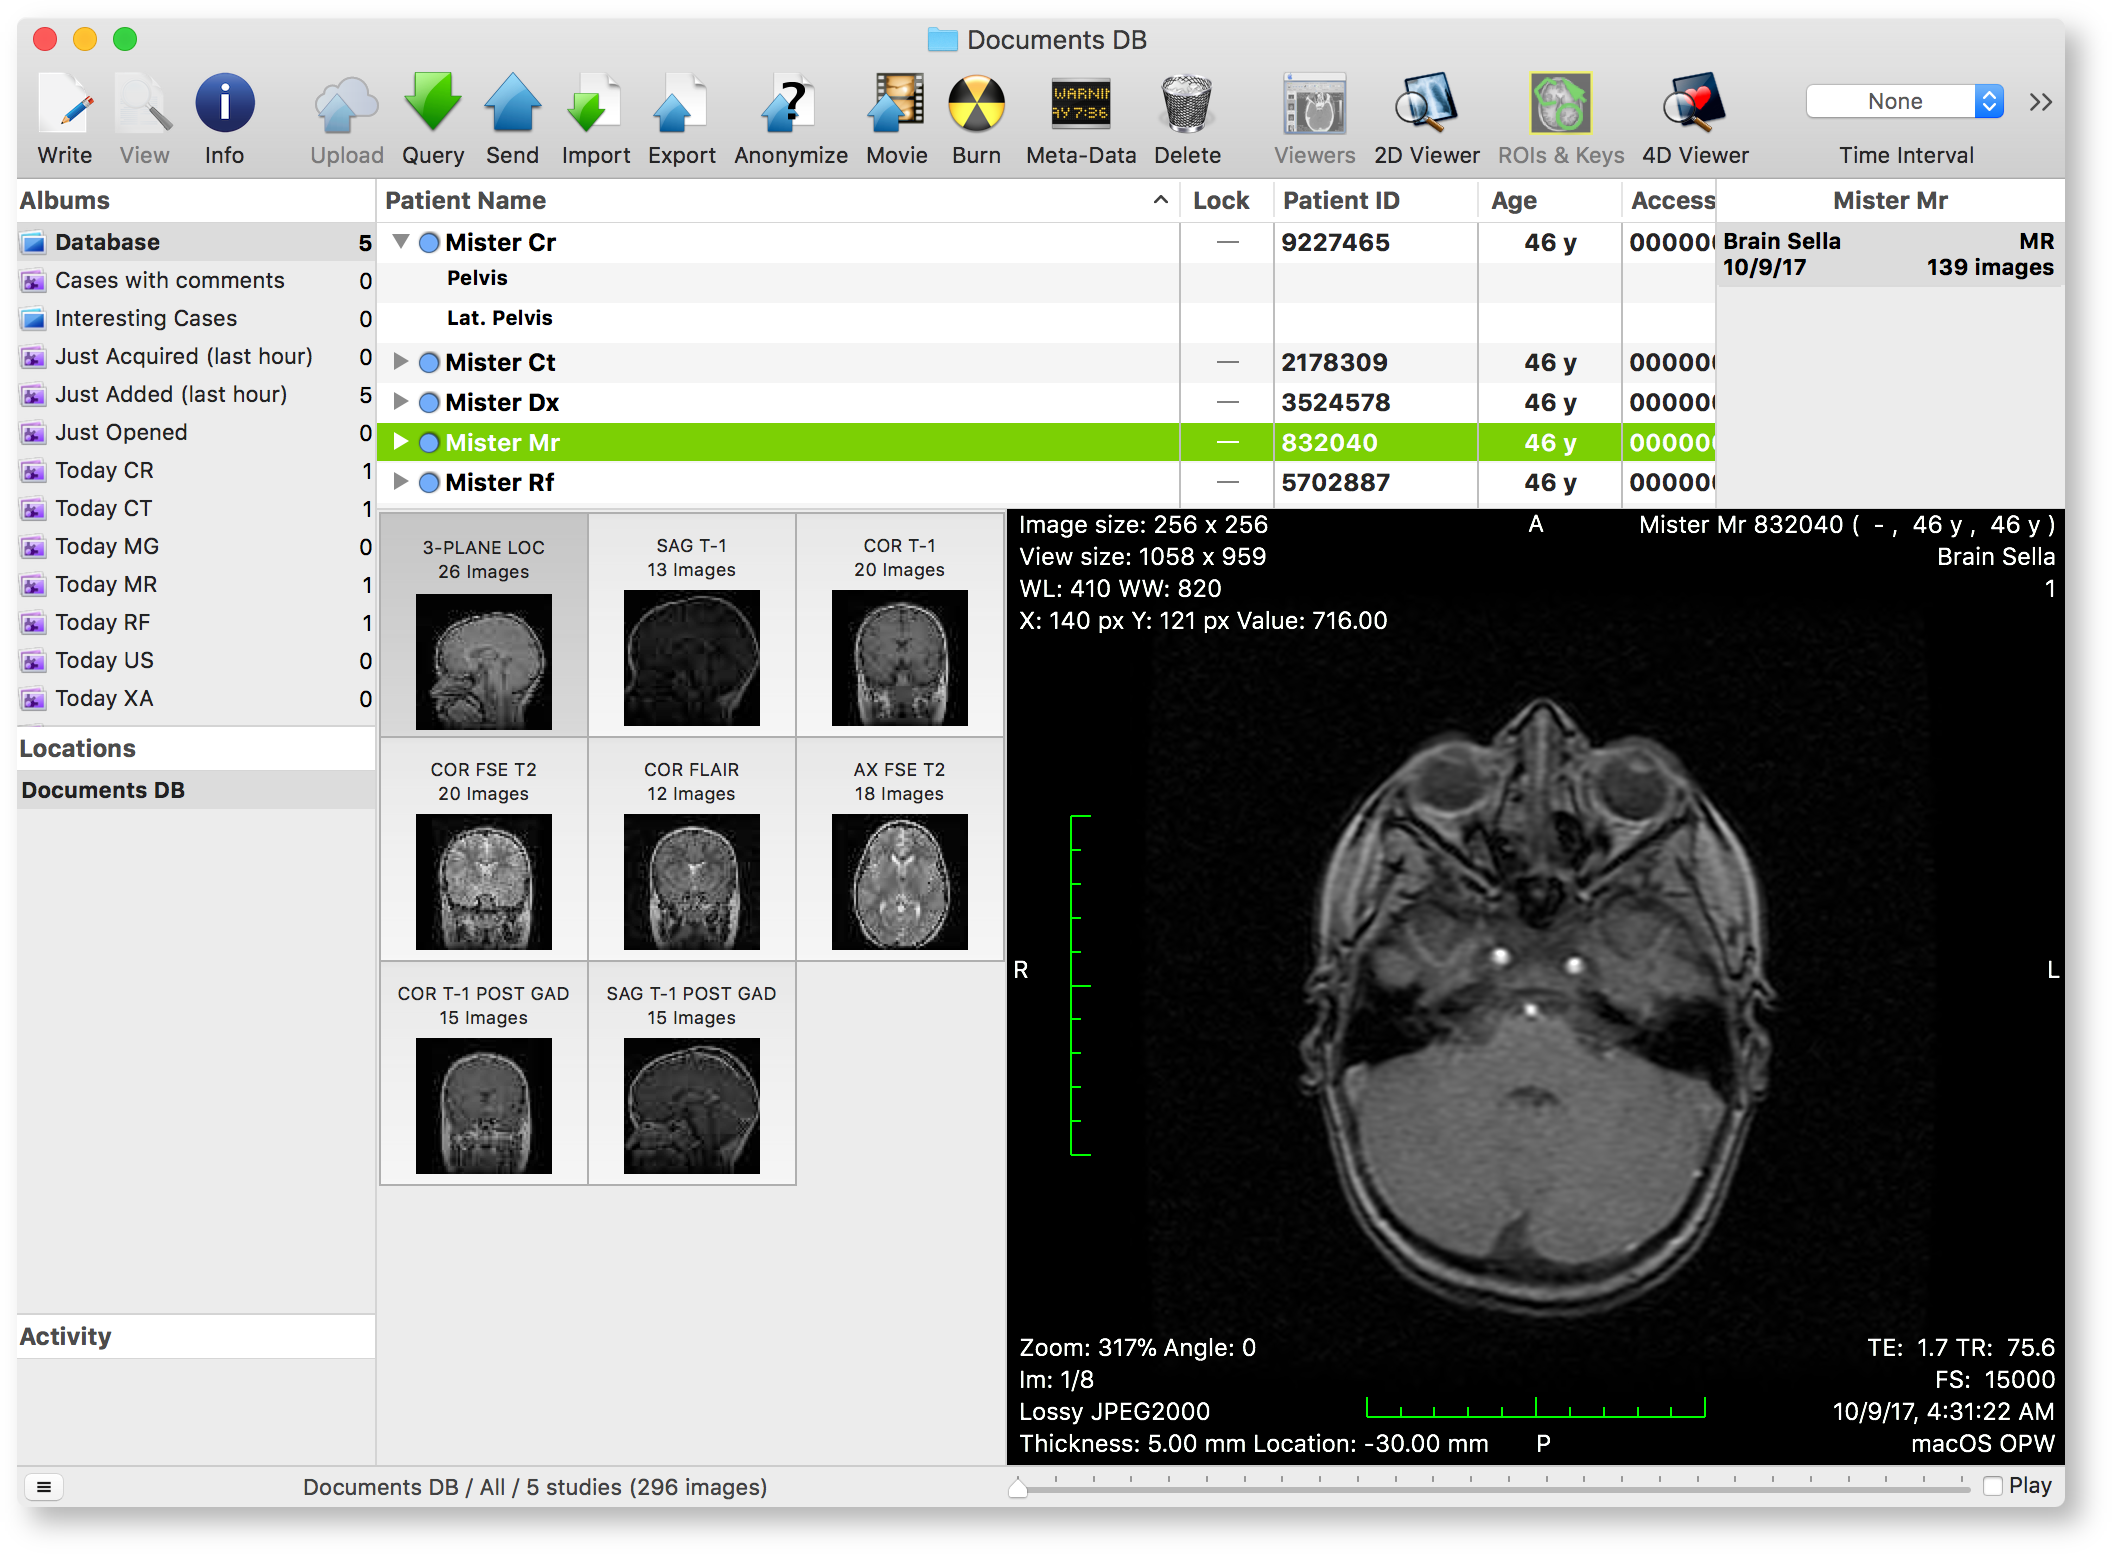

The Database window is the main window in OnePacs Workstation for macOS. The main purpose of this window is to allow you to access and manage the available datasets. When additional studies are imported, they appear in this window.

The main portion of the window is dedicated to the datasets list. Data is organized in an outline view, with a disclosable item for each study. When disclosed, a study displays its series. To the right of the outline, you will find a list of studies that belong to the same patient as the selected items.

The selected studies or series are displayed in more detail in the lower portion of the window, where a grid of thumbnails is displayed on the left side. The selected element in this grid is previewed in the lower right portion of the window.

As the application main window, the Database window also provides quick access to other databases and DICOM nodes, and displays the status of background processes. These extra elements are available in the left portion of the window, along with the albums list. Albums are either user-defined filters (smart albums, displayed with a purple icon) or user-defined collections (plain albums, displayed with a blue icon).